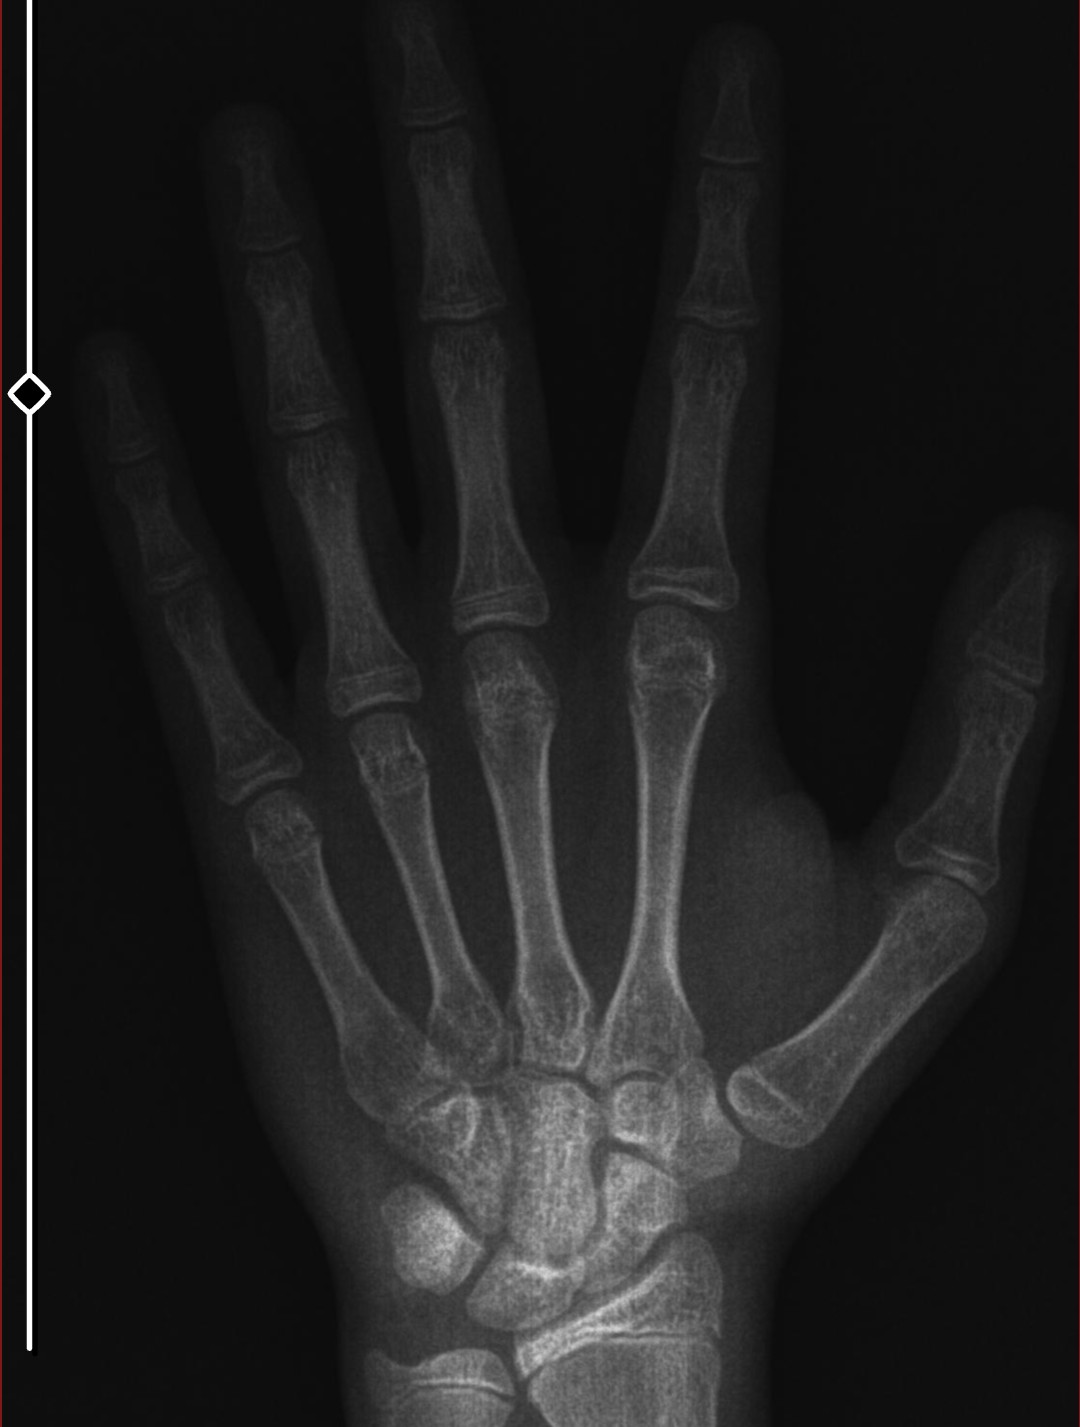

i was 175 while taking this xray (3 months ago) im 15 and almost 16. whags my bone age and whats my estimated adult height.

its closed 175cmi was 175 while taking this xray (3 months ago) im 15 and almost 16. whags my bone age and whats my estimated adult height.View attachment 4256652

idk if this is ragebait or not. i grew 2 centimeters since then and theyre clearly open. i just wonder how much can i grow moreits closed 175cm![]()

Lmao i dont want low iq people's answer on this thread. I already know that my bone age is under 15. Please stfu if u dont know anything about these stuffthey're closed by now